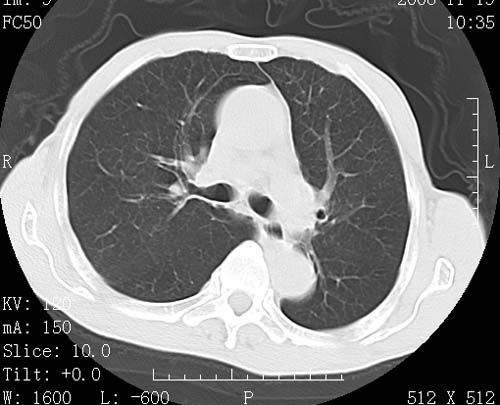

术前查体,双肺部结节是转移?结核?请点评

1)符合食管癌表现。2)两肺及纵隔淋巴结多发性转移瘤。3)左肺上叶舌段及两肺下叶炎症感染。

1)符合食管癌表现。2)两肺及纵隔淋巴结多发性转移瘤。3)左肺上叶舌段支气管扩张伴感染.

食管癌伴双肺转移,评述:肺部毛细血管网丰富,全身血液均快速流经肺部,癌细胞容易过滤定植,形成转移瘤,影象特点为以毛细血管末梢为中心的结节灶,边缘光滑锐利,少见有中心空洞着,不同来源的转移瘤可有各自特点,如甲状腺癌为双肺弥漫性微结节,本例有原发灶,双肺影象灶典型,左肺舌段条带状网格样伴胸膜天幕征,可视为癌性淋巴管炎。

左肺舌段有斑点钙化灶,能否说明是结核而不是转移?如果是转移将放弃手术改成化疗,如果是结核将考虑择期手术